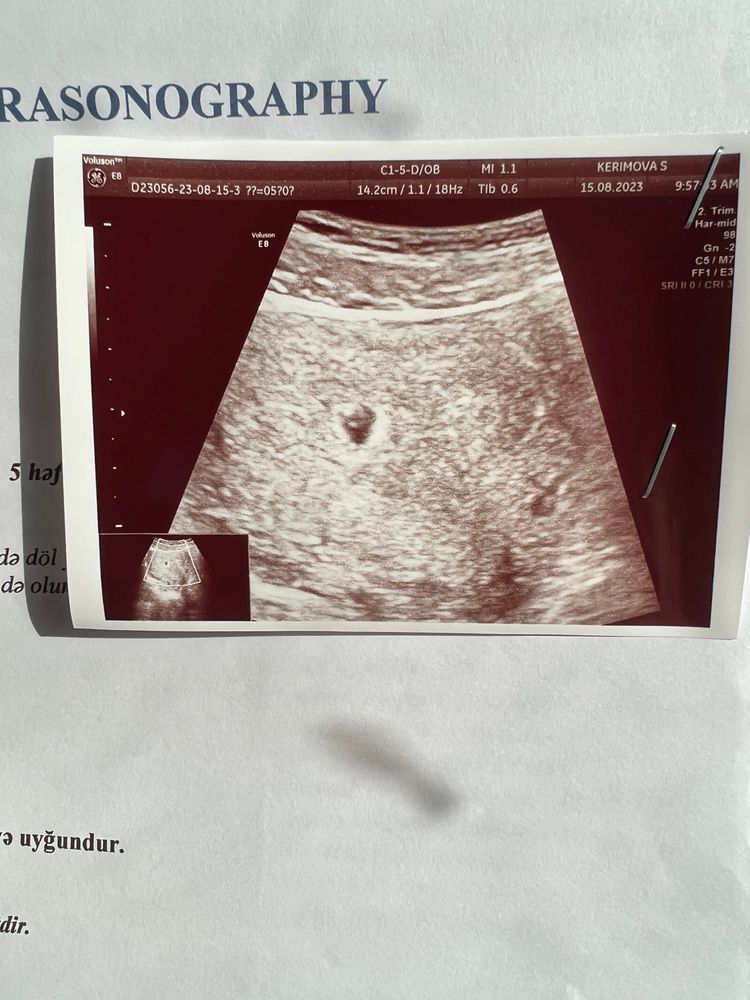

Срок ровно 5 недель, через живот посмотрели. Хотела успокоить себя, что все в матке, а ещё мне дико было надо увидеть жм)) Все на месте❤️